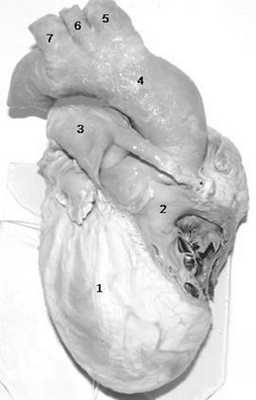

Situs viscerus inversus partialis встречается крайне редко (1 на 10000 живорожденных). При этой аномалии возможно обратное расположение органов только грудной полости (рис.2), или только брюшной полости [5, 9].

(Слева) Фотография, полученная во время аутопсии плода. Выявлены декстрокардия, увеличение и расположение печени по средней линии, незавершенный поворот кишечника. Указанные патологические находки характерны для ППИ.

(Справа) Атрезия легочной артерии. Определяются антеградный кровоток в дуге аорты, ретроградный кровоток к легочной артерии через инвертированный артериальный проток. В норме направление кровотока в артериальном протоке и дуге аорты совпадает.